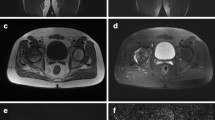

Diffusion changes in the metaphysis were associated with a reperfusion pattern to the epiphysis, increased SI in the metaphysis, and focal physeal abnormalities. Epiphyseal reperfusion patterns, based on observational findings in perfusion MR imaging, were periphyseal in nine patients (Fig. 5) and transphyseal in eight (Fig. 6). Increased metaphyseal diffusion tended to be associated with (p = 0.05) transphyseal pattern of reperfusion to the epiphysis: metaphyseal ADC values greater than 50% over the control side (ADC ratio > 50%) had 13 times greater odds of being associated with transphyseal reperfusion to the epiphysis. The metaphyseal ADC ratio greater than 50% also was associated with an increased T2-signal intensity of the metaphysis (p < 0.001) and the presence of focal physeal irregularity (p = 0.035) (Table 2).

The MR images of a 2-year 11-month-old boy with LCP of the left hip are shown. The (A) ADC map and a (B) gadolinium enhanced fat-suppressed T1-weighted image of the right hip (control side) were compared with a (C) gadolinium enhanced fat-suppressed T1-weighted image of the left hip showing periphyseal reperfusion (arrows) in the epiphysis and the (D) ADC map of the left hip showing increased diffusion to the epiphysis.

The MR images of a 6-year-old boy with LCP of the left hip are shown. The (A) ADC map and a (B) gadolinium enhanced fat-suppressed T1-weighted image of the right hip (control side) were compared with a (C) gadolinium enhanced fat-suppressed T1-weighted image of the left hip showing transphyseal reperfusion (arrows) to the epiphysis and (D) the ADC map of the left hip showing increased diffusion to the epiphysis and the metaphysis.